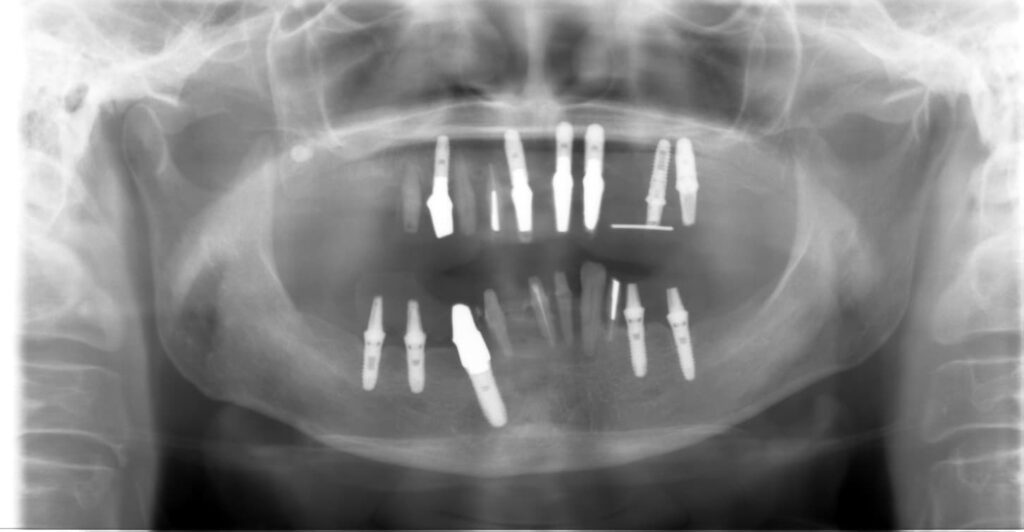

2.精密な検査 レントゲンやCT、お口の中の写真撮影を行い、現状を正確に把握します。